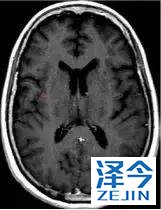

一位77岁的女性患有EPS15-NTRK1 IV期非小细胞肺癌,我们可以看到她的双肺满是病灶,并且出现了肝脏和脑转移,可以说是非常非常晚期了,

肺靶病变达到缓解,我们可以明显的看到前后的图像,病灶明显缩小了,

脑转移病变显示缩小了95%!

初始, 2018年6月 3周期 2018年8月